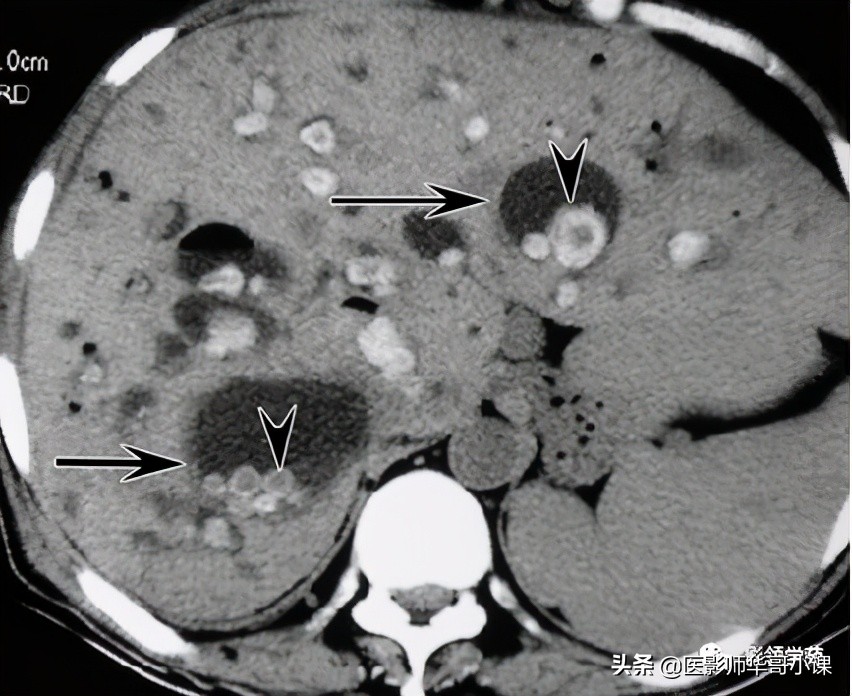

- 部分囊状扩张的胆管腔内有门静脉分支(箭头)

2、“中心点征”是又一重要的征象,是指囊肿阴影内的小点状软组织影像,平扫密度等于或高肝实质,在T2WI序列上呈环状低黑信号,中央区呈圆柱稍高信号,其病理基础是门静脉分支被胆管扩张的囊壁包绕,并在切面上呈轴位投影。Seth等认为“中心点”征象的出现足准确的诊断本病。